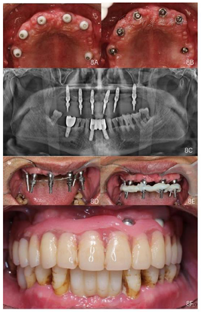

①阿替卡因肾上腺素注射液局麻下拔除13、16,制作上颌过渡性总义齿。②治疗方案设计:拟在12、14、16、22、24、26植入6颗种植体(图4),术前制作种植导板。③13、16牙槽窝愈合6周后,行种植一期手术:16-26牙槽嵴顶全层翻瓣,导板定位定点,16、14分别植入Nobel PCC 4.3 mm×11.5 mm种植体,12、22分别植入Nobel PCC 3.75 mm×11.5 mm种植体,24植入Nobel PCC 4.3 mm×10 mm种植体,26上颌窦外提升植骨,6个月后行种植一期手术,植入Nobel PCC 4.3 mm×10 mm种植体(图5、图6)。④种植二期手术:12、22放置NP30°3.5 mm复合基台;14、24放置RP30°3.5 mm复合基台;16、26放置RP17°3.5 mm复合基台(图7),复合基台均加力至15Ncm。⑤制取种植印模:去除12、14、16、22、24、26复合基台保护帽,放置开口式印模柱,结扎丝连接,3M冠桥树脂固定,制取开口式硅橡胶印模,灌注模型(图8、图9)。

12、14、16、22、24种植一期术后12个月、26种植一期术后6个月,佩戴种植体支持式全牙列固定义齿,义齿戴入后患者唇颊侧丰满度良好,发音清晰,双侧咬合关系恢复良好。曲面体层片示种植体周围骨结合良好(图10)。

面像;E:佩戴义齿前复合基台周围软组织状况;F:下颌

面像;G:戴牙后曲面断层片

面像;G:戴牙后曲面断层片随访及转归:种植体支持式全牙列固定义齿修复后12个月复查:修复体完整稳固,表面及组织面清洁,复合基台周围软组织健康,发音清晰,正中及侧方咬合关系稳定(图11)。曲面体层片示种植体周围无透射影像。

面像;D:右侧咬合像;E:左侧咬合像;F:下颌

面像G:曲面体层片

面像G:曲面体层片下颌自然牙牙周专科检查未探及牙周出血及≥3 mm的牙周袋,牙龈色形质正常。详见牙周大表(图12)。